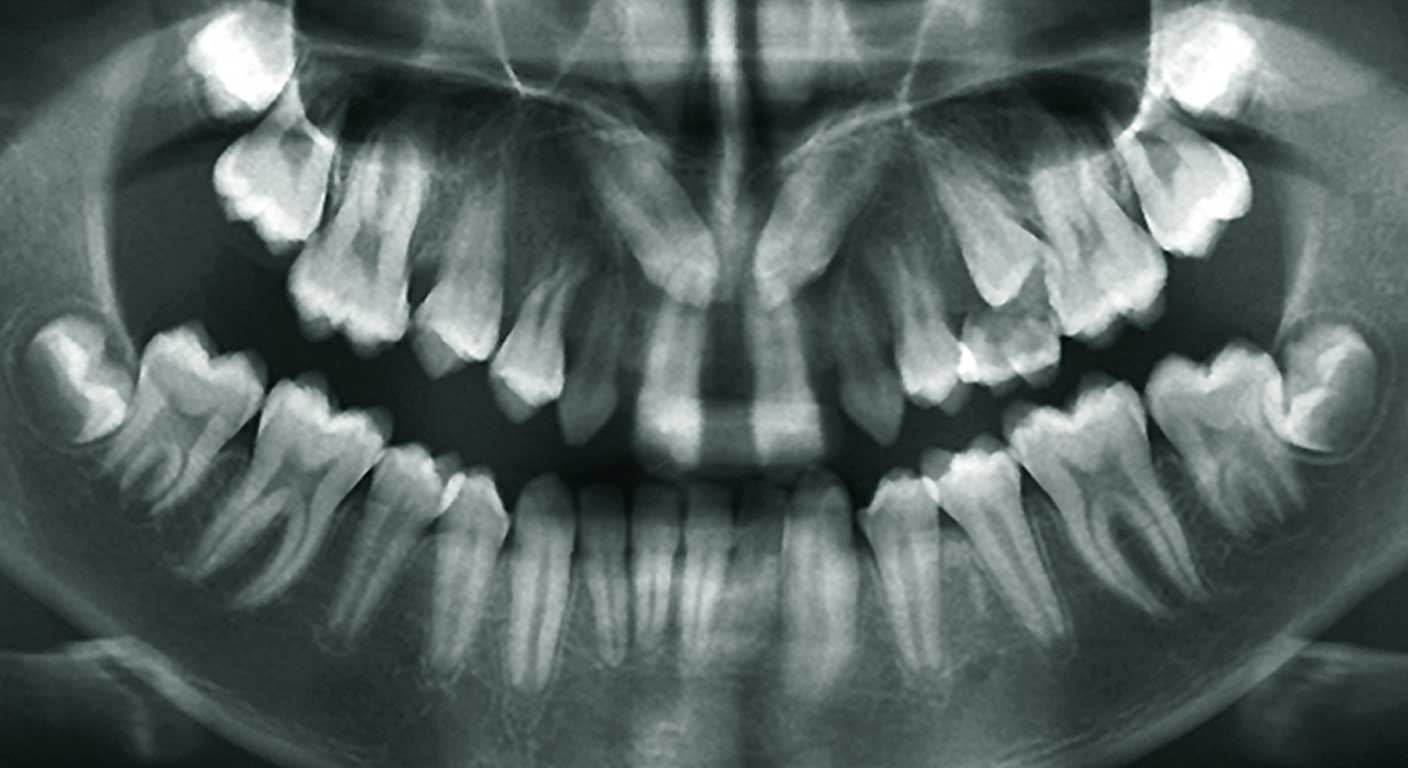

1. عکس پانورامیک (پانورکس):

این عکس که شبیه یک نوار بلند از کل دهان و فک‌هاست، اولین قدم رایج در عکس گرفتن دندان برای ارتودنسی است. در این تصویر تمام دندان‌های بالا و پایین، سینوس‌های فکی، مفاصل فک و استخوان‌ها در یک قاب دیده می‌شوند. این عکس برای شناسایی دندان‌های نهفته (مخصوصاً دندان عقل)، بررسی سلامت اولیه ریشه‌ها و مشاهده کلی ساختار فک ضروری است.